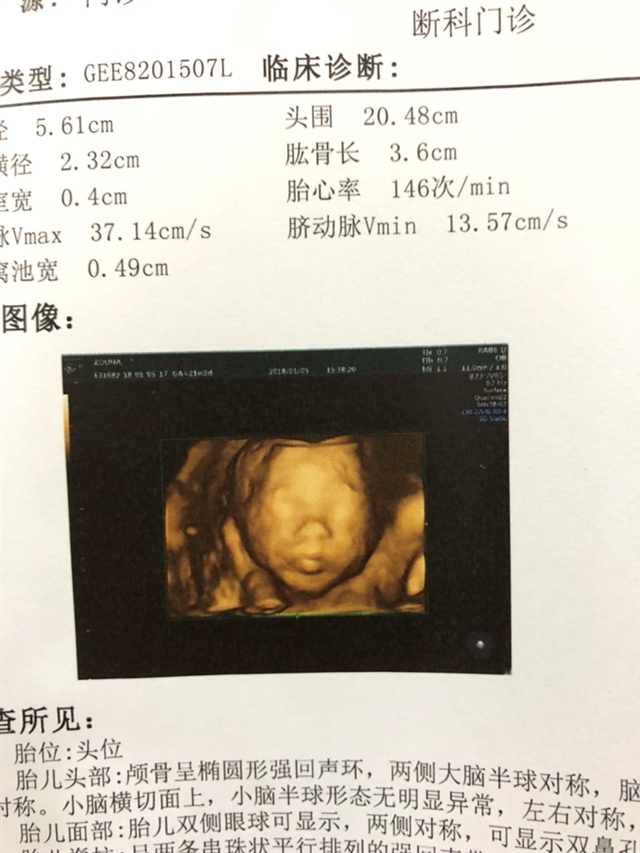

这是做的什么检查?

🕊鹿鹿🕊[帖主]:三维彩超